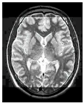

This work collects images from the Kaggle Brain MRI for Brain Tumor Detection dataset, which consists of 253 files with cancer and non-cancer brain images. The sample MRI is illustrated in Figure 2. The dataset has two folders: no tumor encoded as 0 and tumor as 1. The labeled data is more helpful in extracting the patterns from the MRI, which is used to predict the new images related output. The collected image consists of noise information that reduces the performance of brain tumor recognition accuracy. Therefore, image noise should be eliminated to improve the overall prediction efficiency.

Figure 2.

MRI samples Normal Brain MRI (Y1 to Y8) Benign tumor MRI (Y9 to Y15) Malignant tumor MRI (Y16 to Y21).